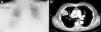

He attended the emergency department due to a decreased level of consciousness, asthenia and drowsiness. Physical examination showed blood pressure 73/47mmHg, heart rate 120beats/min, mild fever and basal oxygen saturation of 86%. He was conscious, prone to bradypsychia and dehydrated. Laboratory tests revealed 59900leukocytes/mm3 with 90% neutrophils and 46000platelets/mm3. Previous tests carried out for regular monitoring of his CMML showed leukocytes 15000/mm3. Chest X-ray showed a rounded high attenuation area in the right hemithorax, with no air bronchogram, measuring 5cm×4cm, on the right parahilar region (Fig. 1a). Blood cultures were drawn and intravenous imipenem treatment was initiated empirically, due to suspected sepsis and pulmonary mass.

Thoracoabdominal computed tomography (CT) was performed (Fig. 1b), showing a heterogeneous mass with marginal spiculation, 5cm in diameter, located in the anterolateral segment of the right upper lobe, with wide pleural contact. Radiologically, the lesion was suggestive of lung neoplasm. Fine needle aspiration was carried out, revealing acute abscessing inflammation associated with a pattern of organizing pneumonia, with no evidence of malignancy. HIV serology was negative. Finally, blood cultures were positive for R. equi.